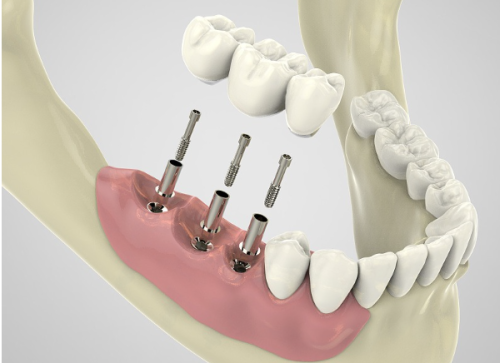

多颗及全口种植牙报价情况

多颗种植牙的价格主要与种植体数目和牙位数有关。需要种植的牙齿越多,费用自然也就越高。全口种植的价格跨度较大,在数十万之间,一般不超过50万元。

对于多颗牙缺失的患者,医生会根据具体的口腔情况制定个性化的种植方案。在这个过程中,种植体的数量和牙冠的选择都会影响更终的种植牙报价。全口种植牙是一项较为复杂的口腔修复项目,它不仅需要考虑种植体的稳定性和功能性,还需要关注美观度和舒适度。因此,全口种植牙的价格相对较高。